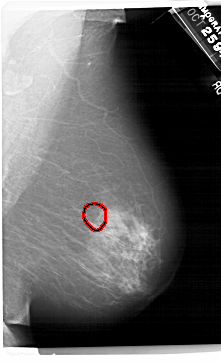

RIGHT_MLO LINES 6871 PIXELS_PER_LINE 4186 BITS_PER_PIXEL 12 RESOLUTION 43.5 OVERLAY

FILE: A_1495_1.RIGHT_MLO.OVERLAY

TOTAL_ABNORMALITIES 1

ABNORMALITY 1

LESION_TYPE CALCIFICATION TYPE AMORPHOUS DISTRIBUTION CLUSTERED

ASSESSMENT 4

SUBTLETY 4

PATHOLOGY BENIGN

TOTAL_OUTLINES 1

BOUNDARY